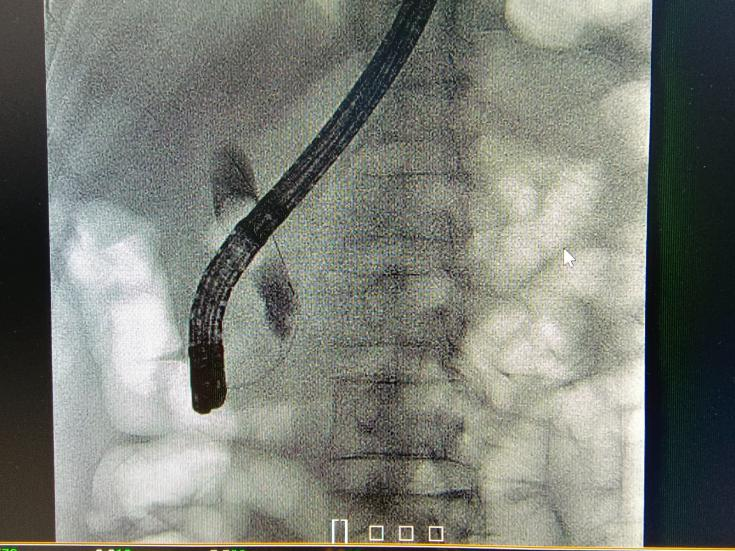

眼看患者情况危急,消化内科一区吴振华主任团队立即决定紧急为患者进行经内镜逆行胰胆管造影微创治疗(ERCP),用十二指肠镜经患者的口部进入,在十二指肠的乳头部进入胰胆管,在放射线造影导引下处理胆管结石,并经口取出。整个微创手术非常成功,术后病人可立即下床活动,发热等症状消失。患者林叔也在不久后康复出院。

“传统的开腹取石术创伤大、术后恢复慢,而ERCP作为目前消化内镜操作中难度最大的技术之一,具有创伤小,病程短,疗效好、并发症少等优点。”吴振华主任表示,“这对于患者也是一个福音,不需要开刀、痛苦小,安全性高、并发症少,从口部就能取出胆结石,还能保留胆管系统完整及生理功能。此外,胆管结石易于复发,如再发结石依然可以选择ERCP取石,而开腹再次手术的困难相对较大。”